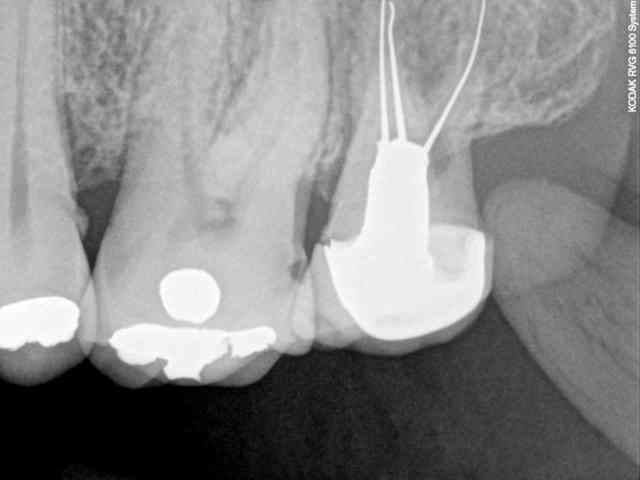

c'est horrible!

je n’arrête pas de trouver des horreurs aux patients.

en deux jours je viens de découvrir des foyers infectieux carabinés à mes patients. des trucs qui passent complètement inaperçus avec des rétro-alvéolaires.

ici, pensez vous que ce soient les cônes d'argents qui soient en cause ?